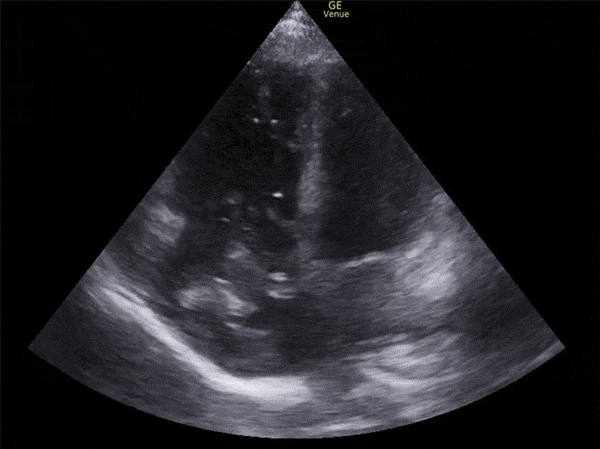

Right Atrial Thrombus

The following two images show clot moving back and forth between the right atrium and the right ventricle. These are free-floating and are often referred to as thrombus-in-transit or clot-in-transit. Unlike mural thrombi these do not form in the heart itself but rather have embolized from a venous thrombus. As the right side of the heart empties by way of the pulmonary artery, these are destined to become pulmonary emboli. The mortality rate of this finding is very high, usually said to be greater than 25%. If you find this, decisions will have to be made about an attempt of embolectomy, anti-coagulation, or thrombolytic therapy.

Notice how large the right ventricle is on the apical four chamber view. A normal right ventricle is ~ 2/3 the size of the left ventricle. In this case, however, the right is considerably larger than the left. In this setting, this finding tells us that the clot in the right atrium is not the first one. This person already has a pulmonary embolism large enough to cause right heart strain.